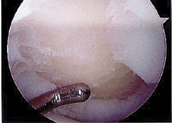

There are three main techniques. The most common, microfracture

chondroplasty, involves drilling small holes in the bone at

the base of the cartilage. This causes bleeding from the bone. The blood

fills the defect and forms a blood clot. Scar tissue replaces the blood

clot, and ultimately the scar tissue is replaced by cartilage. For the

cartilage to grow it needs two things: motion to distribute the joint

fluid and provide nutrition, and the use of crutches to limit the strain

applied to the cartilage while it is growing. This usually means six

weeks of crutches after surgery. The cartilage that grows back is not

normal hyaline cartilage, but rather fibrocartilage or scar cartilage.

It is inferior to the original cartilage, but it can help restore joint

cushioning, reduces pain and improves function. This technique is done

arthroscopically and requires healthy surrounding cartilage to help

bear some of the load for the newly formed scar cartilage.